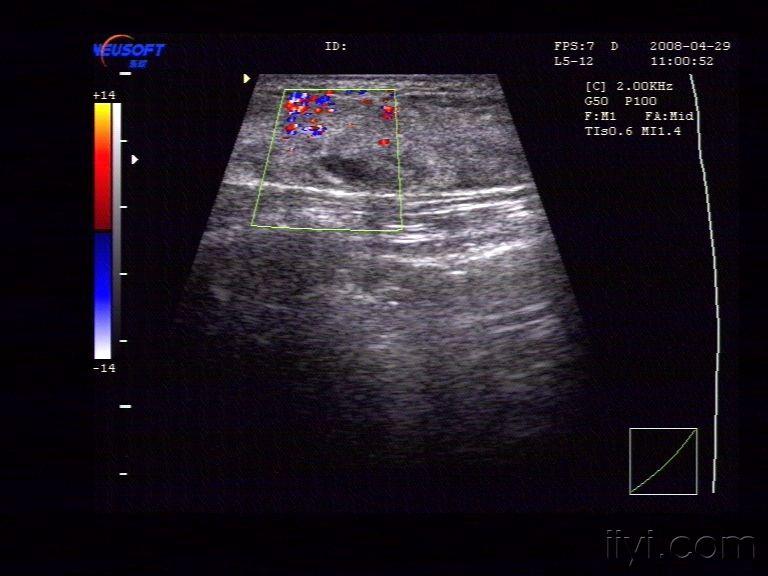

乳腺囊性增生 - 超声医学讨论版 - 爱爱医医学论坛

图片尺寸768x576